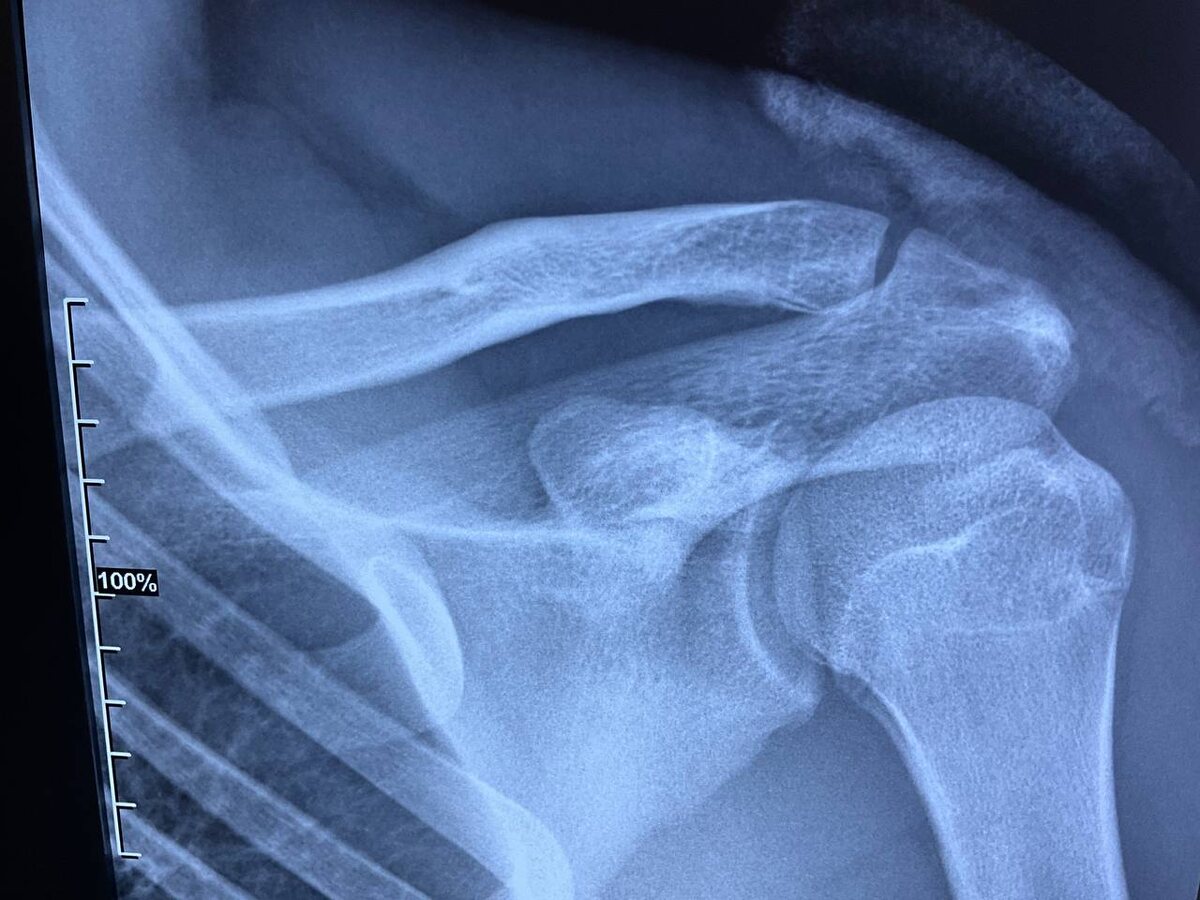

Травма плечевого пояса у спортсменов

Для спортсменов консервативное лечение (без операции) при полных вывихах ключицы (особенно акромиально-ключичного сочленения) сопряжено с рядом специфических рисков, которые могут критически повлиять на спортивную карьеру: Для профессиональных игроков и активных любителей при полных вывихах (III типа и выше) чаще рекомендуется оперативное вмешательство, чтобы восстановить анатомическую целостность и обеспечить стабильность плечевого пояса в условиях высоких нагрузок. Если вам требуется медицинская консультация или постановка диагноза, обратитесь к специалисту.

Для спортсменов консервативное лечение (без операции) при полных вывихах ключицы (особенно акромиально-ключичного сочленения) сопряжено с рядом специфических рисков, которые могут критически повлиять на спортивную карьеру:

Для профессиональных игроков и активных любителей при полных вывихах (III типа и выше) чаще рекомендуется оперативное вмешательство, чтобы восстановить анатомическую целостность и обеспечить стабильность плечевого пояса в условиях высоких нагрузок.